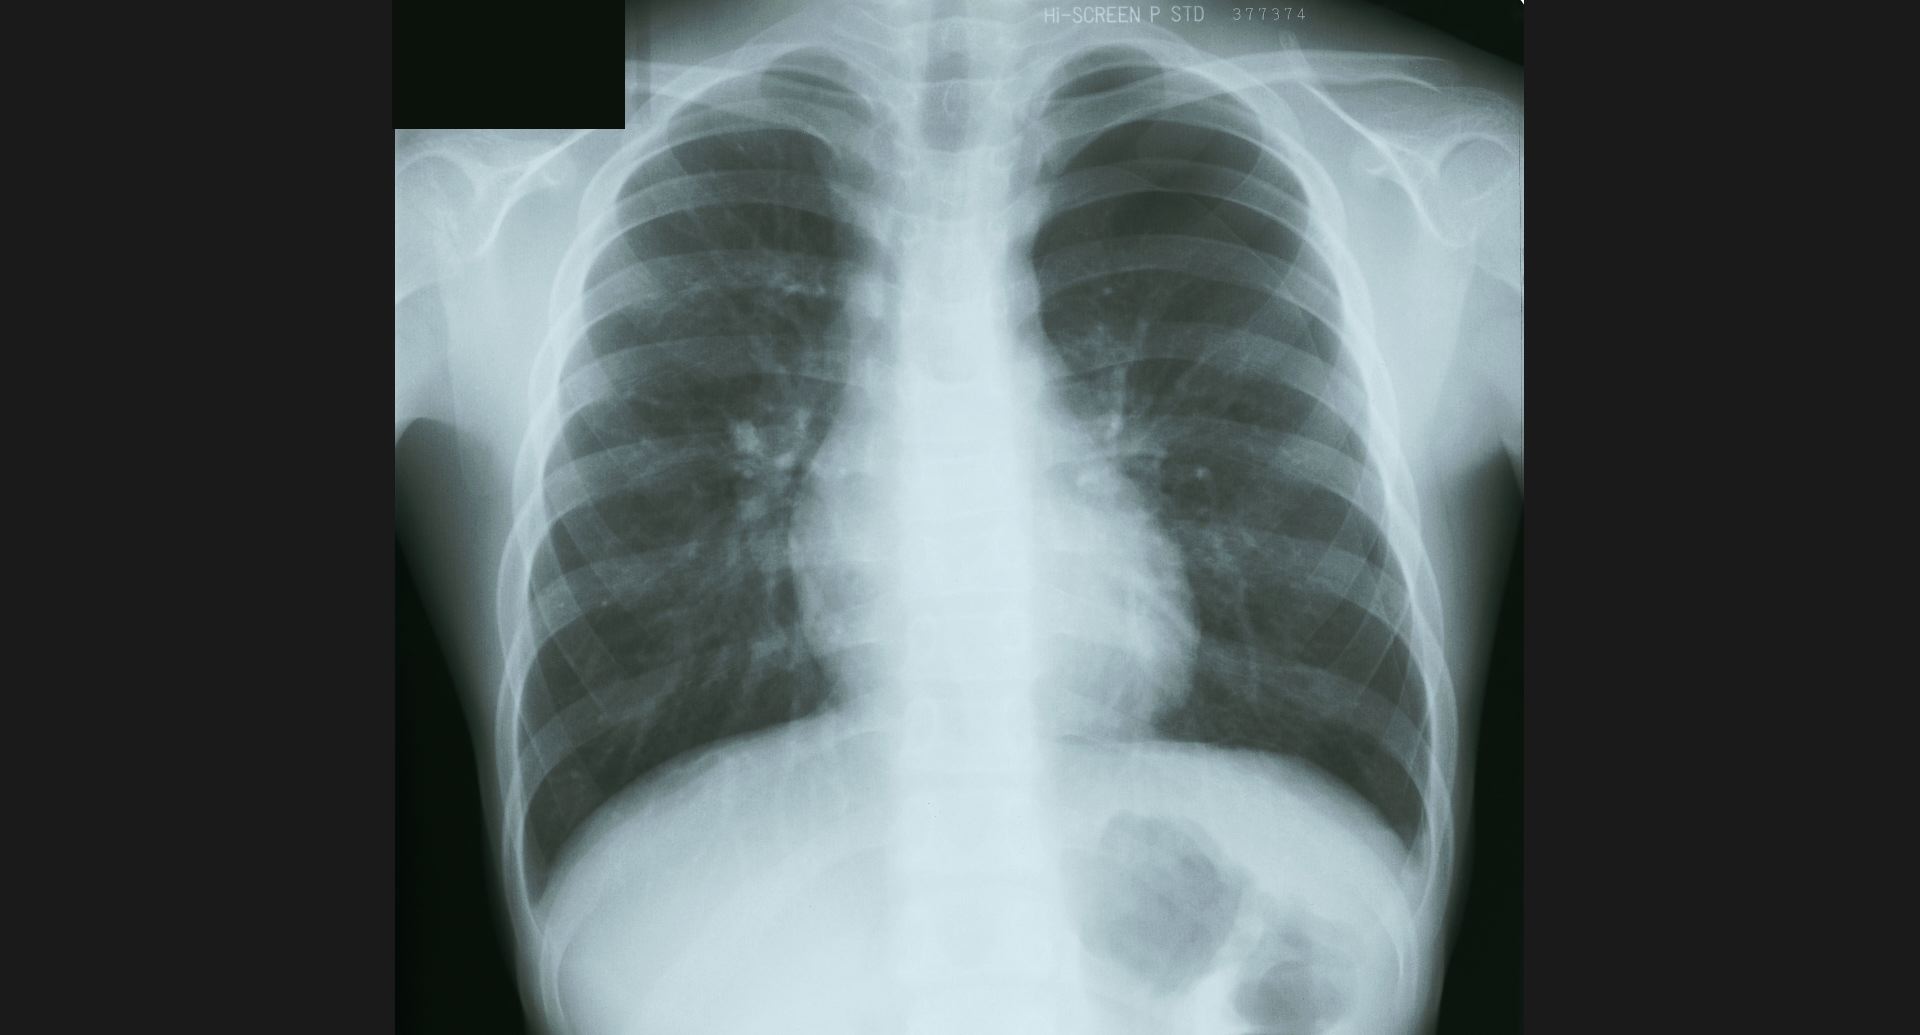

fig.6(97KB)

:Alveolar proteinosis (tomography)butterfly pattern, air bronchogram。